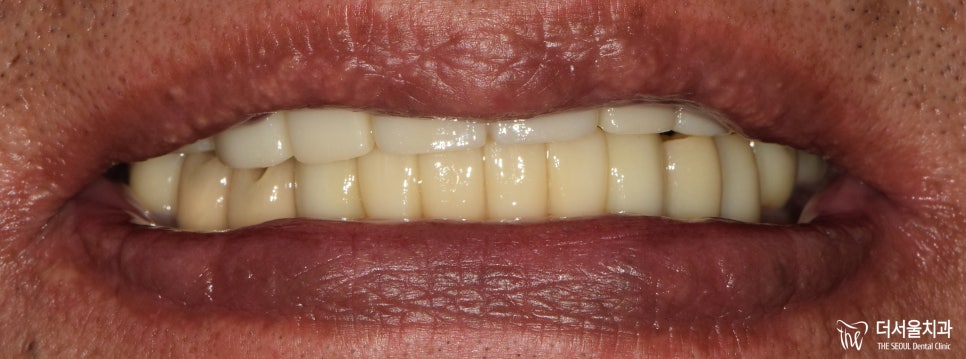

6. 최종 결과

완성된 보철을 전달받은 뒤,

오늘부로 마무리되고

이제는 정상적으로 생활할 수 있다는 것에

그렇게 최종 보철을 세팅하며

꼼꼼하게 조정하고 마무리 지었는데요.

실제로 적용된 모습을 보면,

이전에 있던 진짜 치아랑 별반 다를게 없죠?

기능, 심미성 모두 신경써서

만들어드렸습니다.